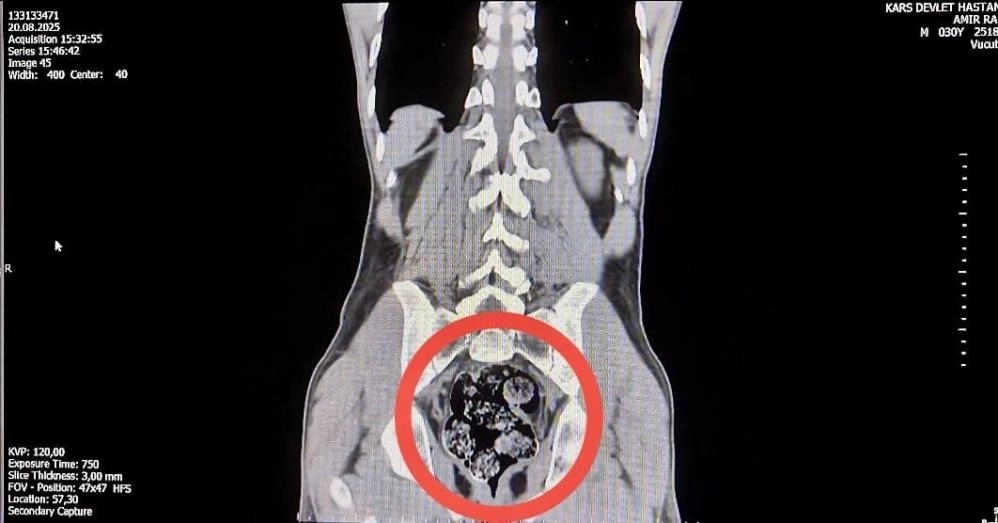

Edinilen bilgiye göre, İl Emniyet Müdürlüğü Narkotik Suçlarla Mücadele Şube Müdürlüğü ekipleri, kentte uyuşturucu ticareti yapılacağı bilgisine ulaştı. Yapılan istihbarat çalışmaları ve takip sonucunda, İran uyruklu Jafar Ayrem (42) ve Amır Rafıeı Shekarbaghanı (34) kuryelerin, otobüs ile uyuşturucu maddeyi kente getireceği tespit edildi.Bunun üzerine harekete geçen narkotik ekipleri, Iğdır'dan Kars'a seyir halindeki yolcu otobüsünü takibe aldı. Narkotik ekipleri daha sonra önceden belirlenen noktada, yolcu otobüsüne operasyon düzenlendi.Düzenlenen operasyonda, İran uyruklu kuryeler gözaltına alındı.İl Emniyet Müdürlüğü'ne getirilen ve durumundan şüphelenilen kuryelerden Shekarbaghanı, detaylı arama için Kars Harakani Devlet Hastanesi'ne götürüldü. Hastanede yapılan emar ve röntgen kontrollerinde şüphelinin makatında cisim olduğu belirlendi. Yapılan cerrahi müdahalede, şüphelinin makatından 7 parça halinde 203,02 gram metamfetamin çıkarıldı.Gözaltına alınan şüpheliler, emniyetteki sorgusunun ardından 'uyuşturucu veya uyarıcı madde ticareti yapma veya sağlama' suçundan adliyeye sevk edildi. Mahkemeye çıkarılan şüpheliler, tutuklanarak cezaevine gönderildi.